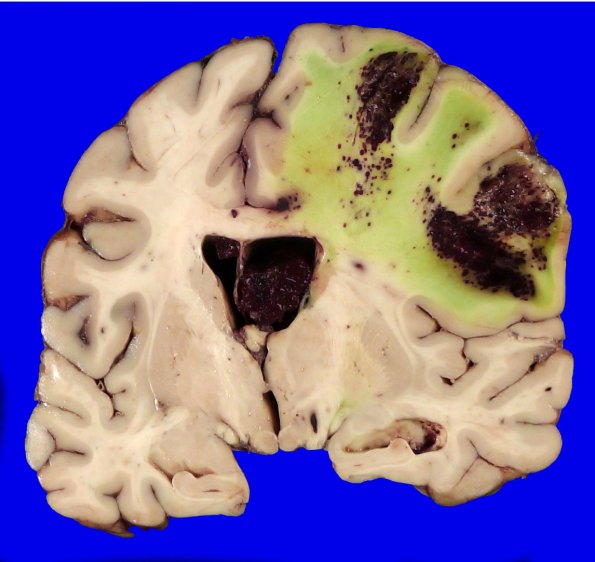

Washington University Experience | VASCULAR | Hemorrhage, hypertensive | 49B3 A20-76_8

49B3,4 This is an unusual hemorrhage for a purely hypertensive pathogenesis; however, this patient has severe coagulopathy superimposed on longstanding cirrhosis and chronic kidney disease.